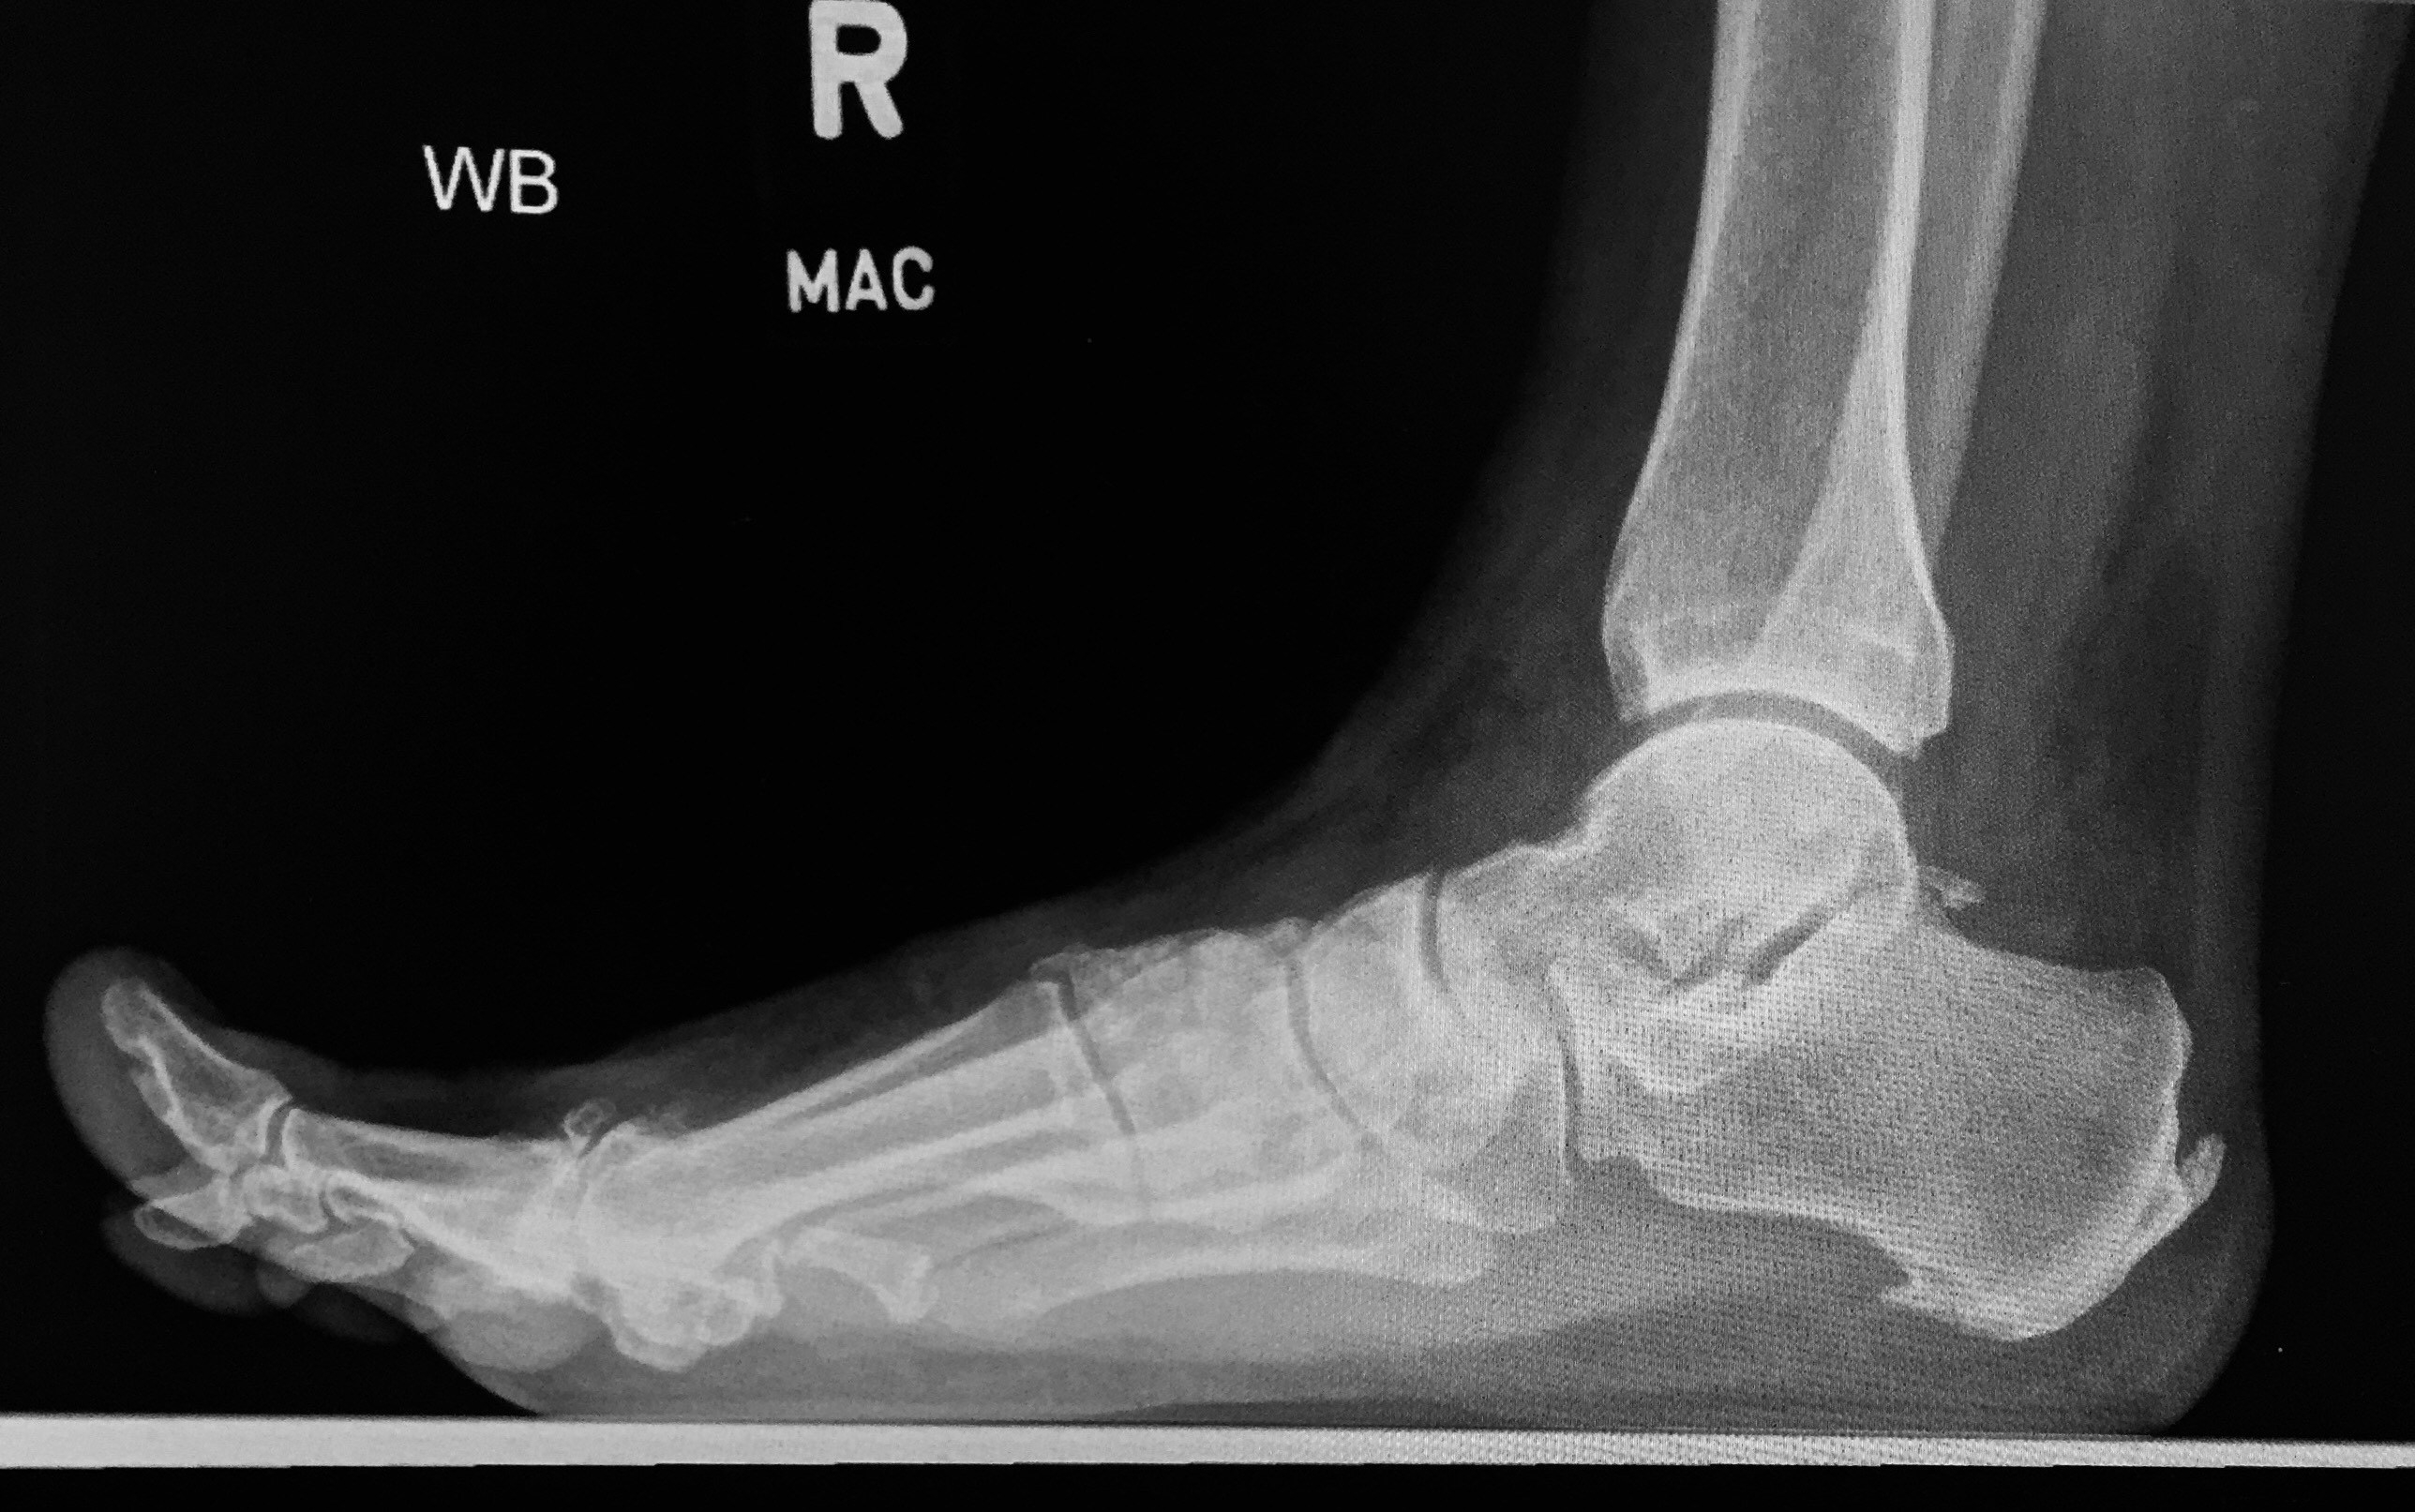

This is a Lateral view of a painful arch, Right foot.